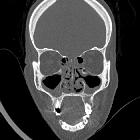

CT

- non-contrast CT

- sinonasal mucosal thickening +/- air-fluid levels +/- soft tissue nodules

- bony/cartilaginous erosions, in particular, affecting lamina papyracea, nasal septum, and lateral nasal cavity wall +/- perforation